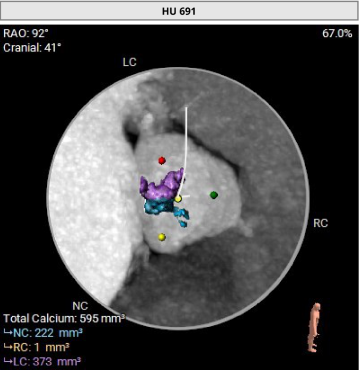

1. Type 1 型二叶式主动脉瓣,瓣叶增厚伴中度钙化,L-N间钙化融合嵴,左室流出道呈敞口型;

冠脉阻挡风险及钙化评估

• Type1型二叶式主动脉瓣,L-N间可见钙化融合嵴,瓣叶增厚伴中度钙化,综合预估瓣膜锚定难度尚适中,瓣膜植入后受钙化融合嵴挤压影响存在形变及移位的风险,瓣周漏、瓣中瓣风险适中;